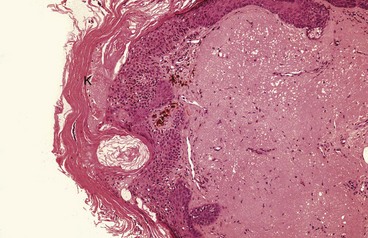

Fig. 46.4 Solar keratosis—histopathology

Occurring in sun-exposed areas, this lesion typically shows thickening of the keratin layer K. Epidermal cells can show a range of atypia, which may amount to squamous cell carcinoma-in-situ. The dermis shows severe solar damage

Characteristic histological features are marked thickening of the keratin layer (hyperkeratosis) and prickle cell layer (acanthosis). There is a variable degree of dysplastic change and abnormal mitotic activity deep in the epidermis. These features suggest malignant transformation but, importantly, the basal layer remains intact.